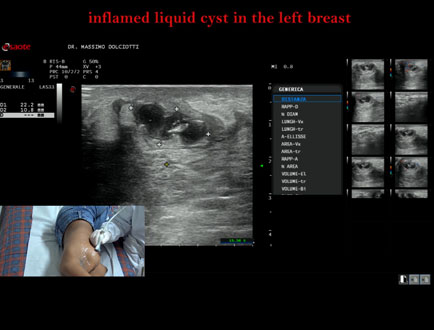

Data inserimento: 07/10/2025

Ecografia del: 15/05/2025

Strumento: Esaote MyLab Eight

Sonda: Lineare Multifrequenza 3-13 MHz

Età Paziente: F 16 anni

Motivazione dell'esame: da 2 giorni dolore alla mammella sinistra.

Commento all'esame: le immagini ed il video documentano al quadrante inferiore esterno ore 4 della mammella sinistra, formazione disomogenea ipoanecogena, delle dimensioni di 24 x 14 mm, da ricondurre a cisti liquida infiammata.

Conclusioni: cisti liquida flogosata alla mammella sinistra (inflamed liquid cyst in the left breast).

Presentazione: Dr. Massimo Dolciotti - Ancona